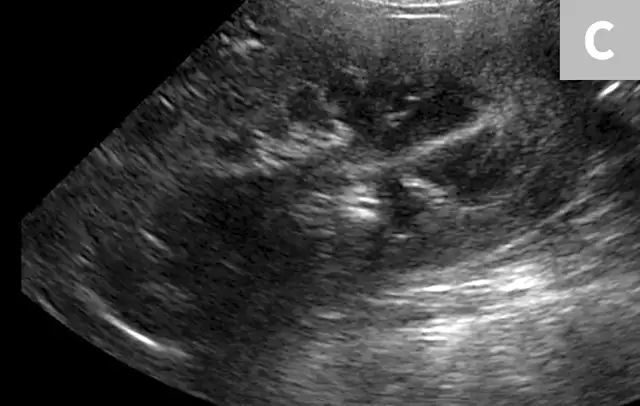

FIGURE 6A

1 / 2

Mild to moderate right hydronephrosis and proximal ureteral dilation in a Dalmatian.